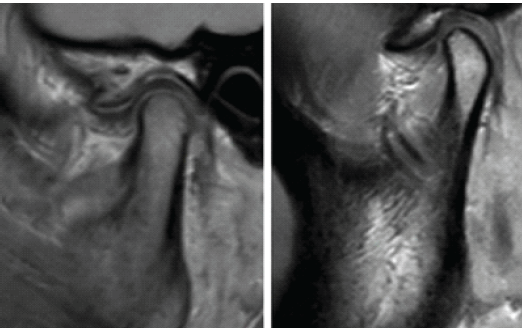

- Disc displacement: Anterior/posterior disc position relative to the condyle (Fig. 1).

Figure 1: Temporomandibular joint magnetic resonance imaging evaluation with arthritis seen in the joint space.